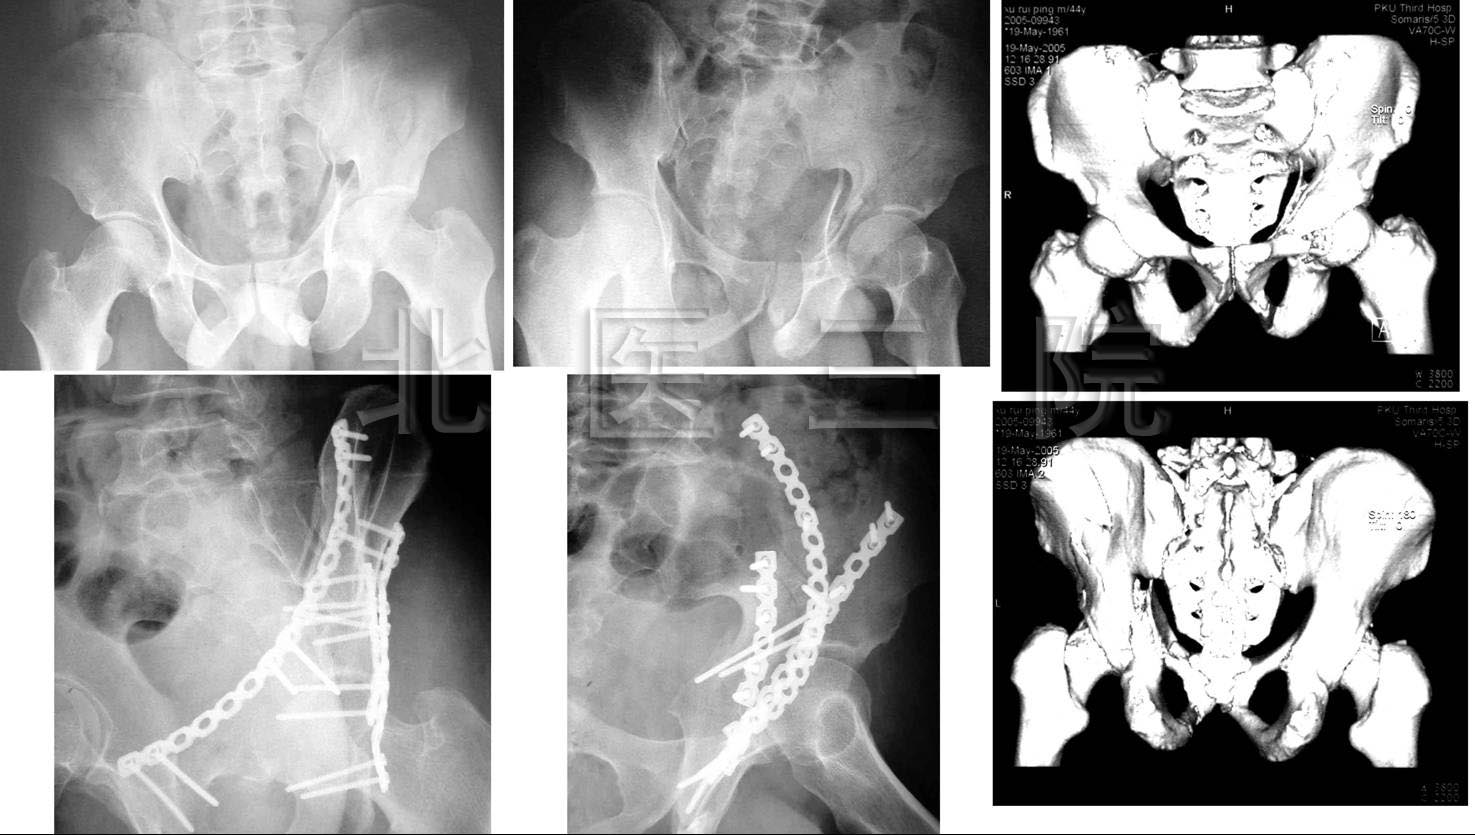

图为:骨盆髋臼骨折经皮微创固定

FIGURE: Percutaneous fixation of pelvic ring and acetabulum fractures.

8.男,44岁,高处坠落伤致左髋臼、骨盆骨折